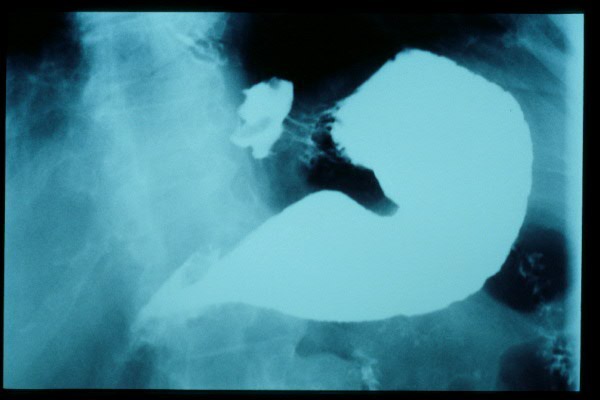

Hernia de hiato gigante.

Hernia de hiato por deslizamiento al TGED.

Hernia de hiato por deslizamiento al TEGD.